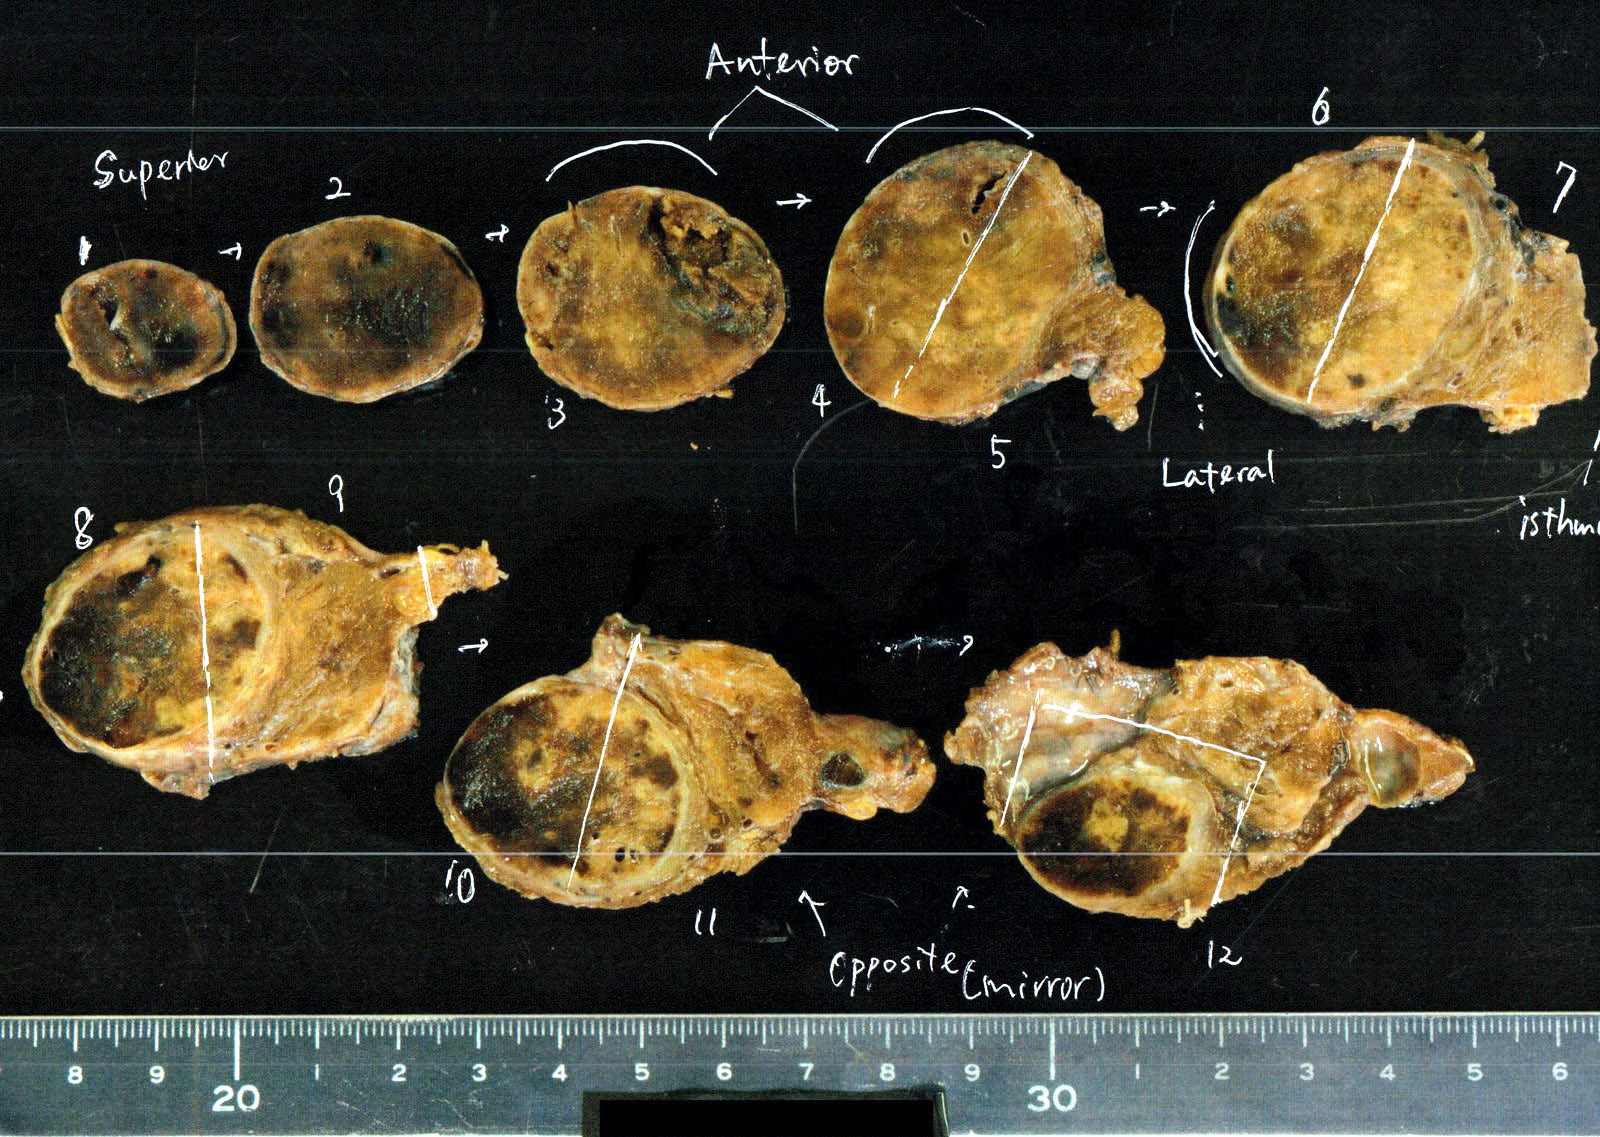

Gross description

- Solitary, encapsulated nodule; multiple if familial

- Variable size (1 - 10 cm)

- Solid, gray-white, tan to light brown

- Secondary changes: hemorrhage, cystic change, fibrosis, calcification, infarction; may develop post-fine needle aspiration cytology

- Rarely black; especially seen with minocycline therapy

Gross images

Contributed by Andrey Bychkov, M.D., Ph.D., Mark R. Wick, M.D. and AFIP

Images hosted on other servers: